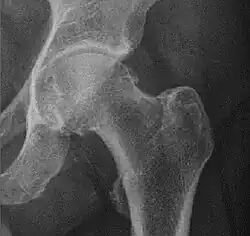

X-ray of hip dysplasia

X-rays of hip dysplasia are one of the two main methods of medical imaging to diagnose hip dysplasia, the other one being medical ultrasonography.[1][2] Ultrasound imaging yields better results defining the anatomy until the cartilage is ossified. When the infant is around 3 months old a clear roentgenographic image can be achieved. Unfortunately the time the joint gives a good x-ray image is also the point at which nonsurgical treatment methods cease to give good results.